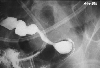

Ischemic colitis

A case of ischmic ileitis due to ileus symptoms.

X-ray

Inflammatory or ulcerative disease / lesions/Ischemic colitis